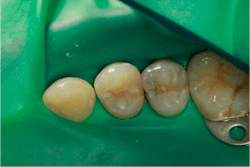

A rubber dam is applied and both lesions are prepared (figure 5).

After both teeth are prepared, we can see that these were large, deep lesions. An indirect pulp cap is placed over the pulp using a light-cured, flowable material (Theracal LC by Bisco) (figure 6).